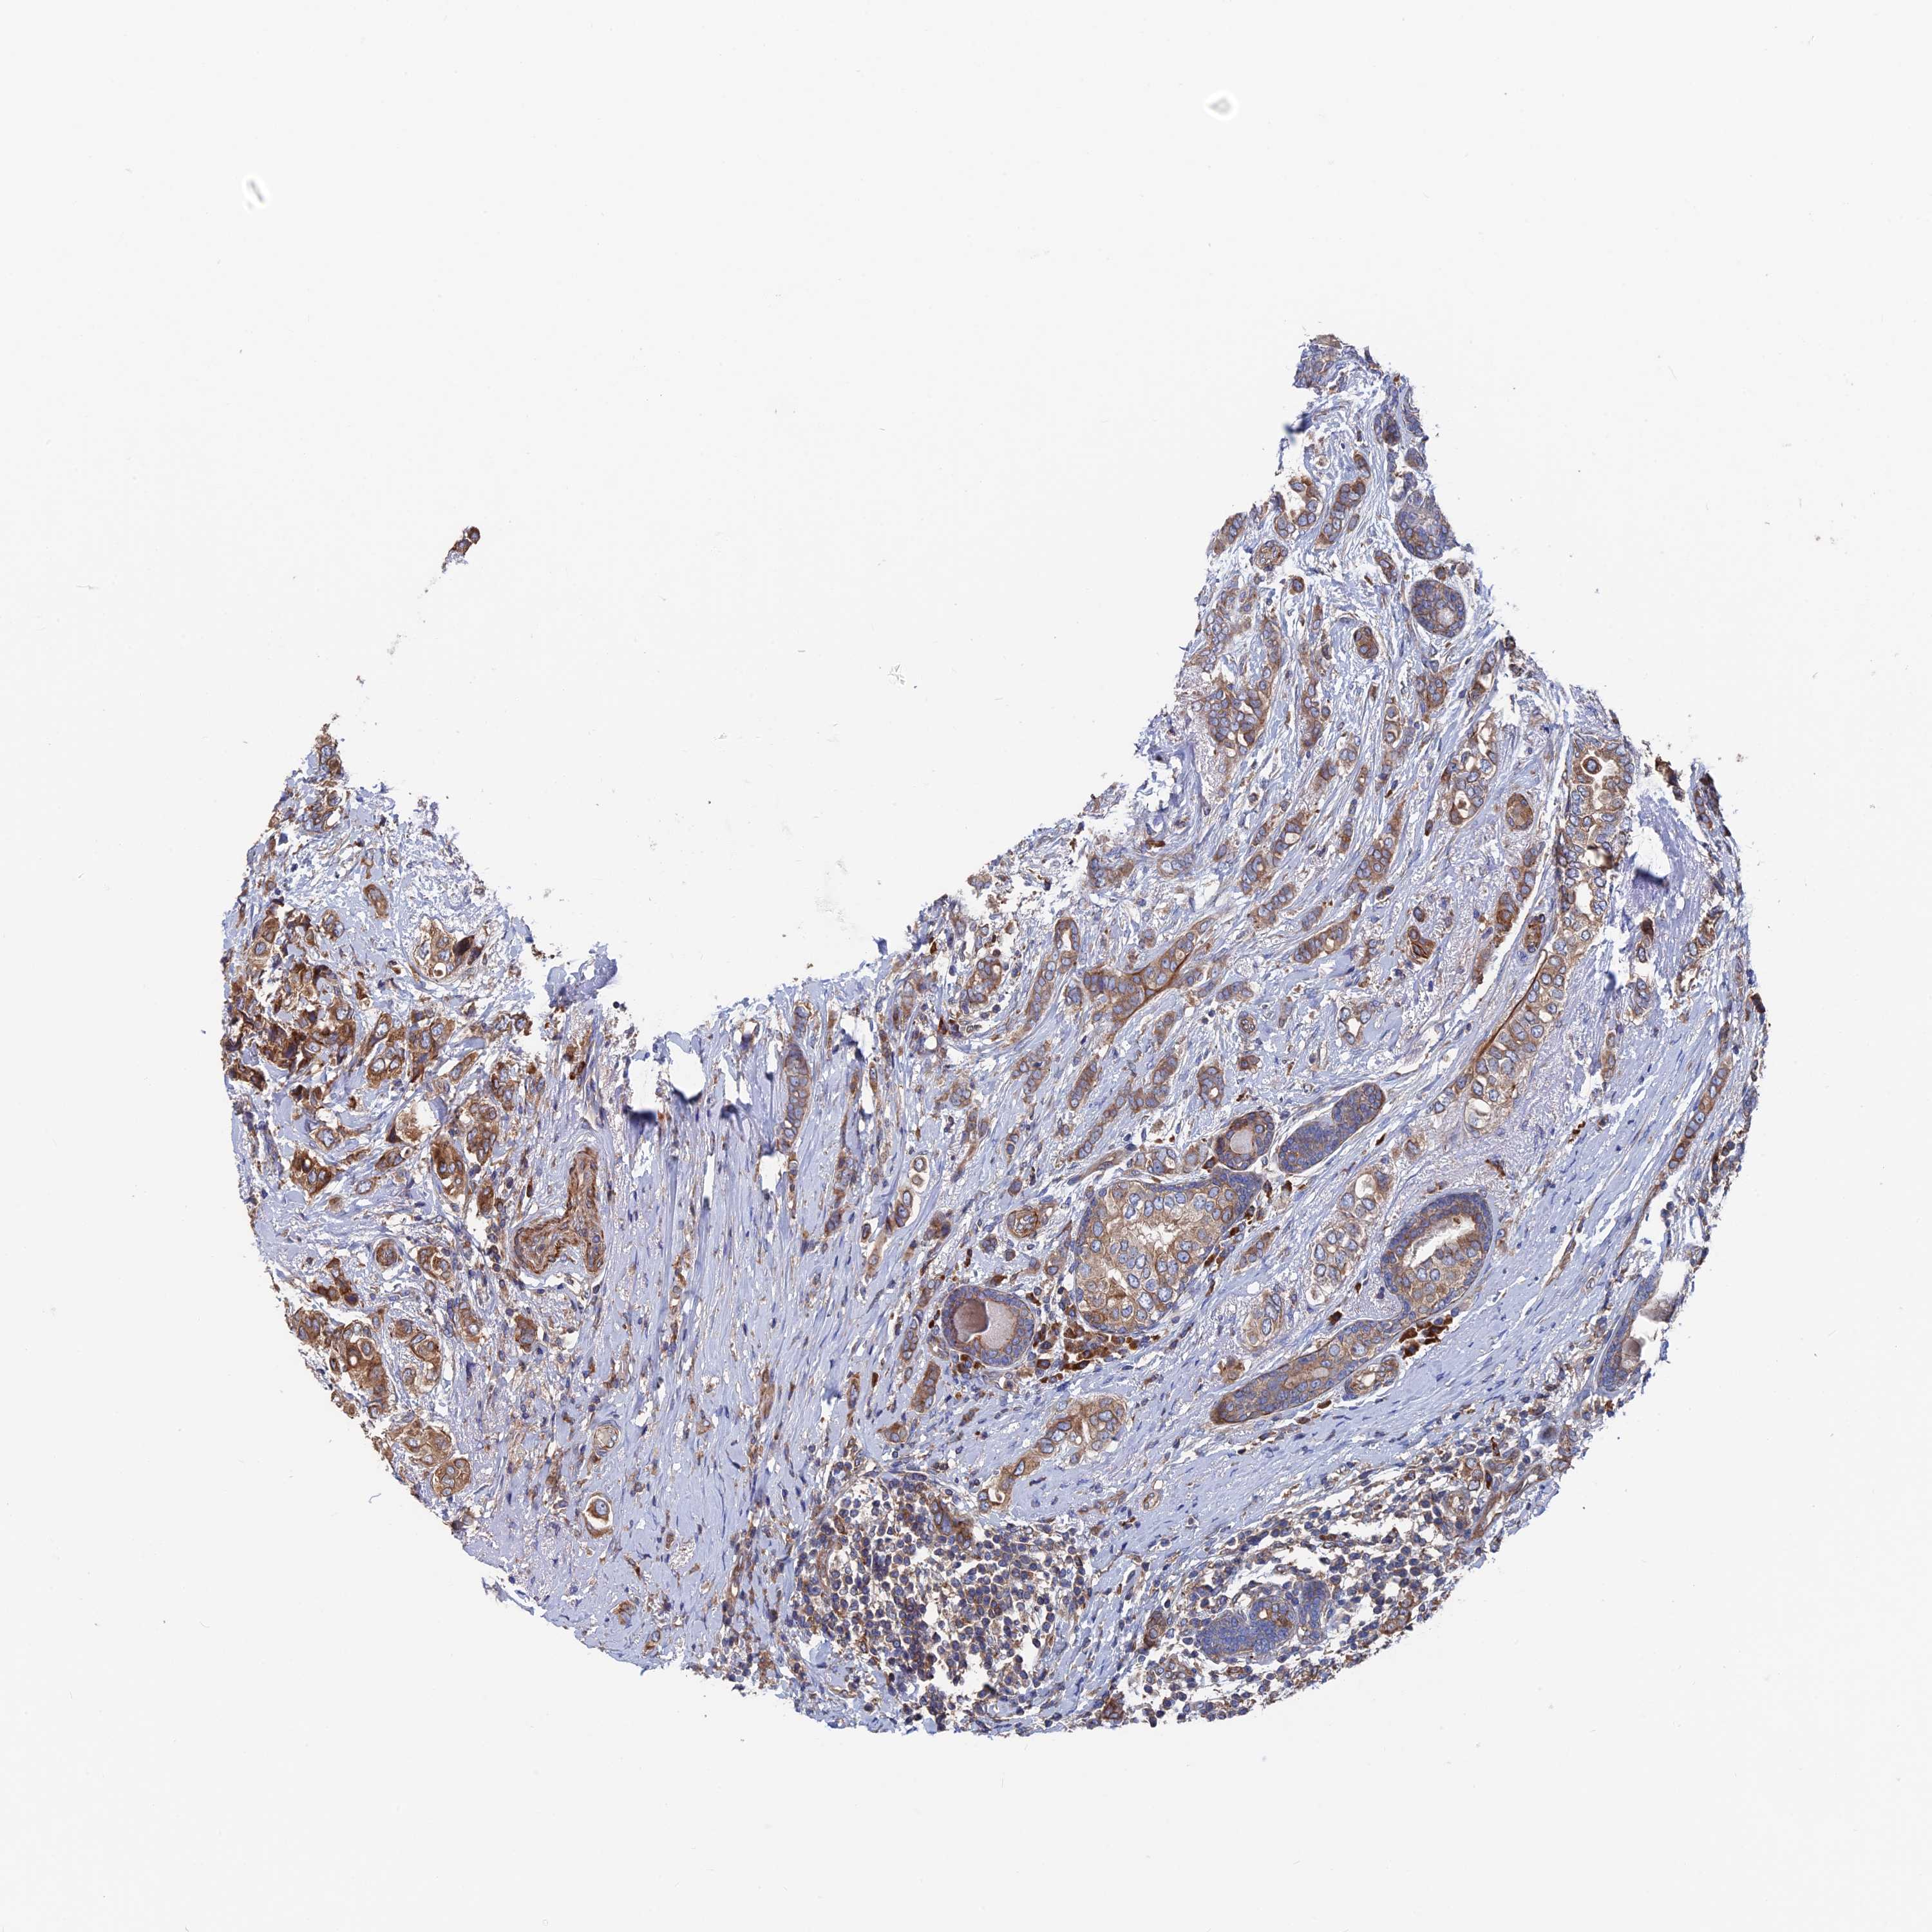

CANCER BREAST CANCER Show tissue menu

BRCA TCGA BRCA VALIDATION PROTEIN EXPRESSION